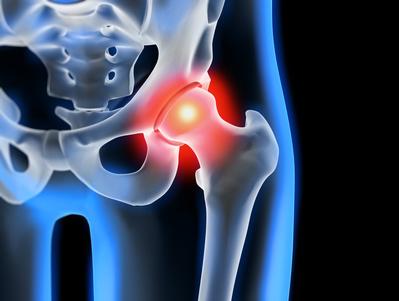

Hüftschmerzen mit Ausstrahlung ins Bein können verschiedene Ursachen haben und den Alltag der Betroffenen erheblich belasten. Das Hüftgelenk ist eines der größten Gelenke im menschlichen Körper und besteht aus der Hüftgelenkspfanne und dem Oberschenkelkopf. Es ist ein Kugelgelenk, das sich in der Leistenregion zwischen Beckenknochen und Oberschenkelhals befindet.

Das Hüftgelenk wird von einer Gelenkskapsel, Muskeln, Sehnen und Schleimbeuteln umgeben. Der Gelenksknorpel überzieht das Hüftgelenk und sorgt für eine reibungslose Bewegung. Wenn Probleme im Hüftgelenk auftreten, können sie Schmerzen verursachen, die ins Bein ausstrahlen.

Die häufigste Ursache für Hüftschmerzen ist jedoch Abnutzung und Verschleiß am Hüftgelenk, auch als Hüftarthrose bekannt. Dies tritt meistens im fortgeschrittenen Alter auf, kann aber auch jüngere Menschen betreffen. Neben der altersbedingten Abnutzung können Verletzungen, Unfälle, angeborene Fehlstellungen, Stoffwechselerkrankungen und Überbelastung zu Hüftgelenksarthrose führen.